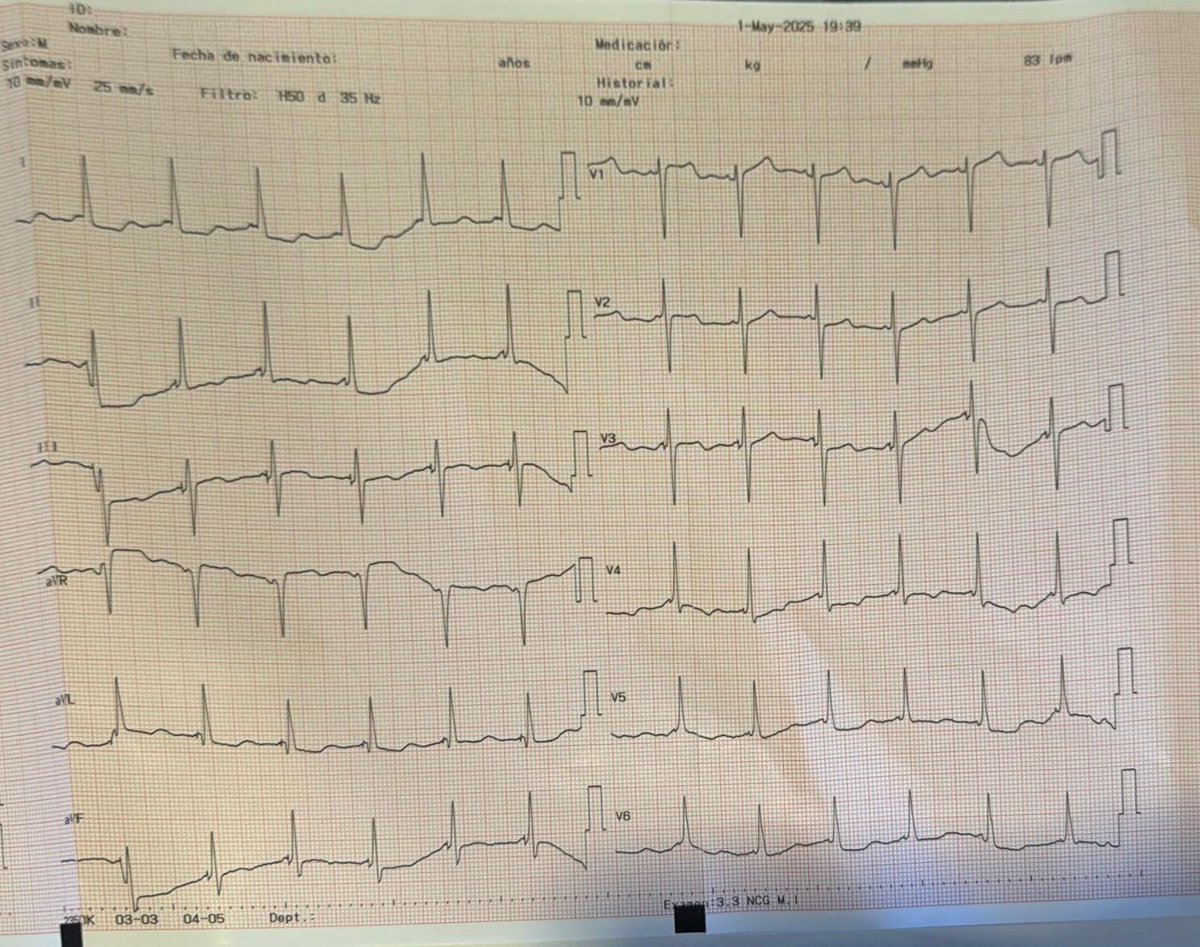

78 y.o. female NIDCM, LVEF 28%, severe mitral regurgitation, LBBB. His-bundle resynchronization. Hisian threshold with correction of LBBB-> [email protected] ms (48 hour later). Improvement in interventricular synchrony demonstrated on UHF-ECG. Baseline and post-CRT recordings are shown